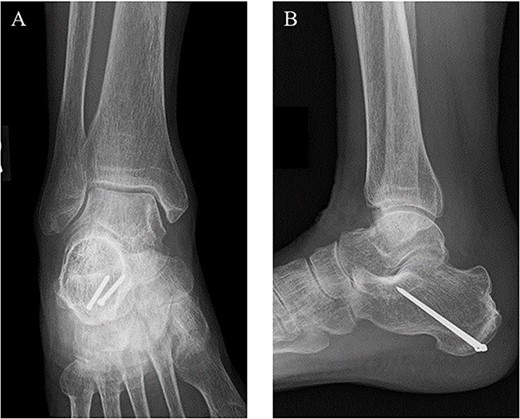

A 78-year-old woman complained of right heel pain when tripping during walking and visited to our hospital. She had medical histories such as arrhythmia, hypertension and hyperlipidemia. Physical examination revealed swelling, subcutaneous bleeding and tenderness on the posterior aspect of her heel and Thompson test was positive. Plain radiographs of the right ankle showed an avulsion fracture of the calcaneal tuberosity (Fig. 1). Non-contrast computed tomography (CT) demonstrated that the bone fragment was displaced. Based on medical histories, physical examination and image findings, we diagnosed an avulsion fracture of the calcaneal tuberosity and applied surgical treatment for the patient.

Plain radiographs of the right ankle showed no abnormal findings in (A) an anteroposterior view, but an avulsion fracture of the calcaneal tuberosity (B) a lateral view.